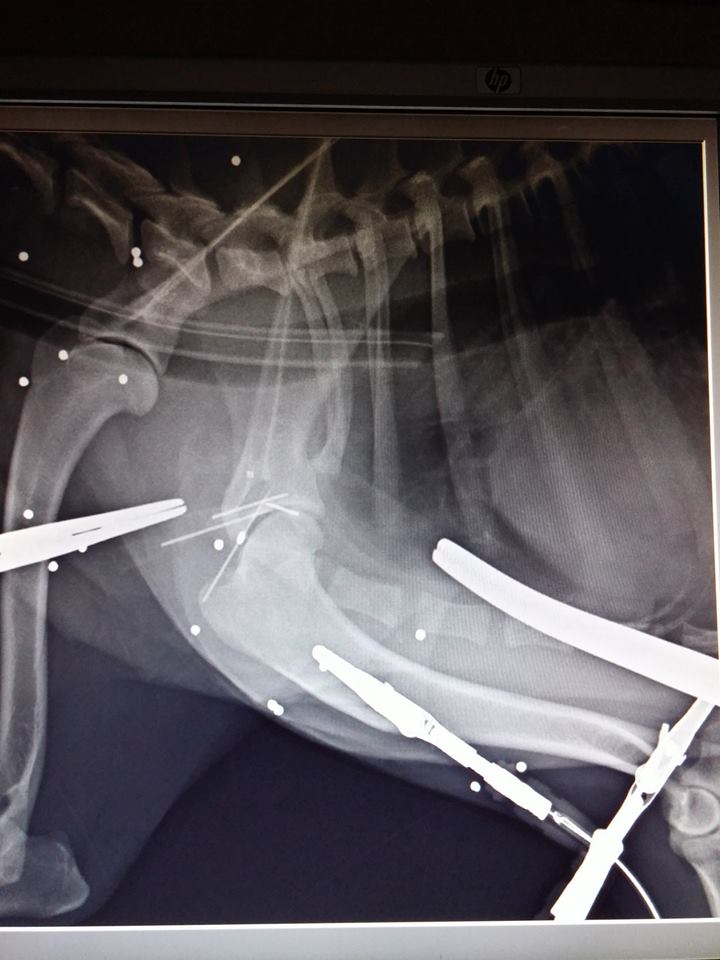

• Ο Μπενυ: Τριγυρνούσε αδέσποτος στην πλατεία Κυπαρισσίας και δέχτηκε πυροβολισμούς. Χειρουργήθηκε και πλέον αναρρώνει. Χρειάζεται βοήθεια για την κάλυψη των εξόδων του 2ου χειρουργείου.